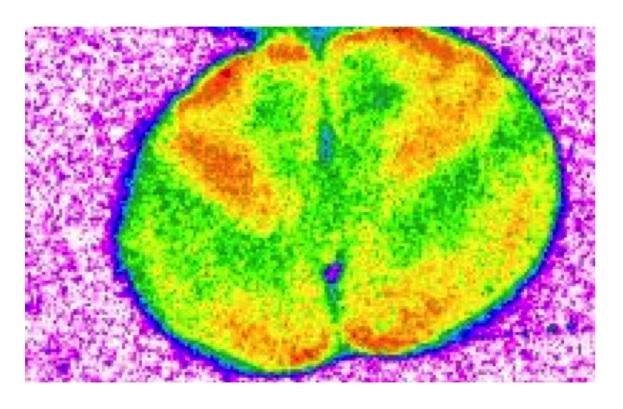

- l'imagerie cérébrale montre également que le médicament altère la fonction de zones cérébrales clés impliquées dans l'apprentissage et la mémoire ;

- de plus, l'exposition à long terme au médicament nuit à la capacité de ces zones cérébrales impliquées dans l'apprentissage et la mémoire à communiquer entre elles (cf visuel).